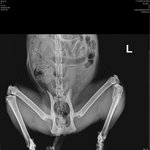

길고양이 수술 시키고싶습니다 도와주세요

길냥이 '행운' 모금내역 공유합니다 :)